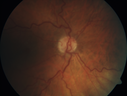

70 year old woman lost vision 12 years ago in her left eye. VA 20/32 OD; 20/800 OS (PPRCA) is a rare disorder of unknown etiology Pigment accumulation along the distribution of retinal veins Finding are usually incidental with minimal effect on vision Often bilateral Associated with Uveitis Sarcoidosis Behcet’s disease Syphilis Measles Rubeola tuberculosis

Pigmented Paravenous Retinochoroidal Atrophy - Left Eye441 views70 year old woman lost vision OS 20 years ago.00000